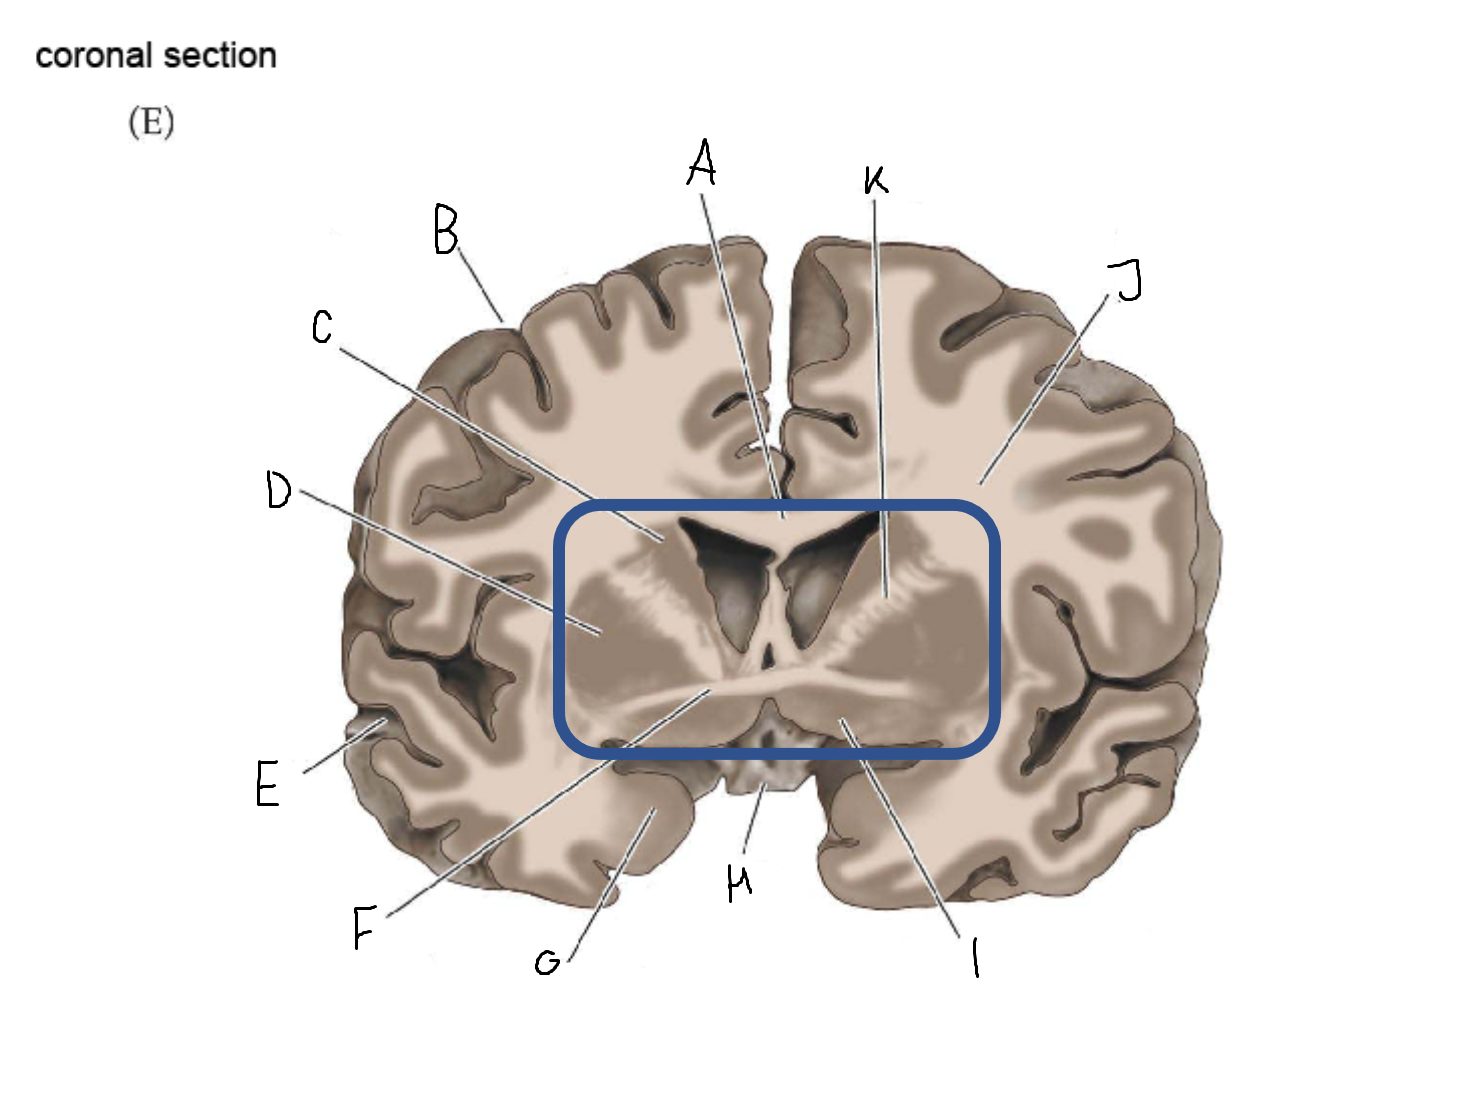

A

corpus callosum

B

lateral ventricle

C

internal capsule

D

third ventricle

E

tail of caudate nucleus

F

lateral ventricle

G

hippocampus

H

mammillary body

I

fornix

J

globus pallidus

K

putamen

L

caudate

M

thalamus

N